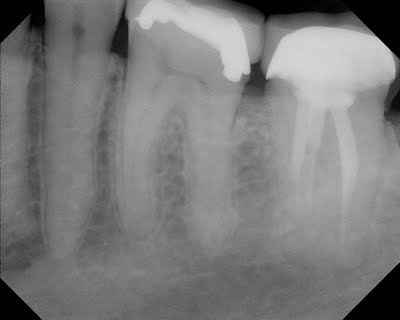

This patient presented with complaint of pain in lower left quadrant. Recent crown prep on #19. Regular diagnostics were inconclusive as to the source of this pain (#19 was testing normally to vitality, probing and percussion testing) A short obturation of #18 was noted, but this tooth was asymptomatic. After short period of time waiting to see if symptoms localized, and failure to do so, a CBCT scan was acquired to evaluate if there was apical bone loss associated with one of these teeth that would help in the diagnosis.

CBCT did not show any radiographic lesions on #18 or #19. The temporary crown #19 was removed for additional pulpal testing. Tooth #19 gave no response to cold on the buccal side and a vital response on the lingual side. It was decided that endodontic treatment should be initiated on #19 with a probable “partially necrotic” pulp.